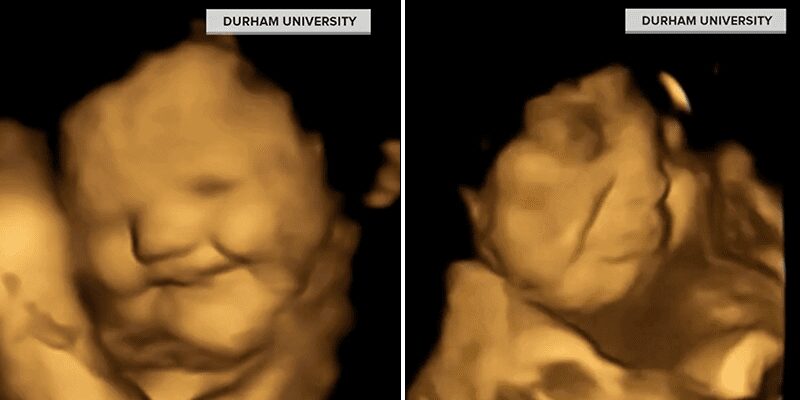

The images came from a study conducted at Durham University and published in the British journal Psychological Science. The study recorded how 100 preborn babies at 32 and 36 weeks reacted to different tastes and smells in their mothers’ wombs.

Researchers discovered that babies in the womb have already developed their own food preferences. One unborn baby was recorded smiling when her mother consumed carrots but made a frowning face when she consumed kale.

Graduate researcher Beyza Ustun, who spearheaded the Durham University study, explained the purpose of her work, saying, “a number of studies have suggested that babies can taste and smell in the womb, but they are based on post-birth outcomes while our study is the first to see these reactions prior to birth.”